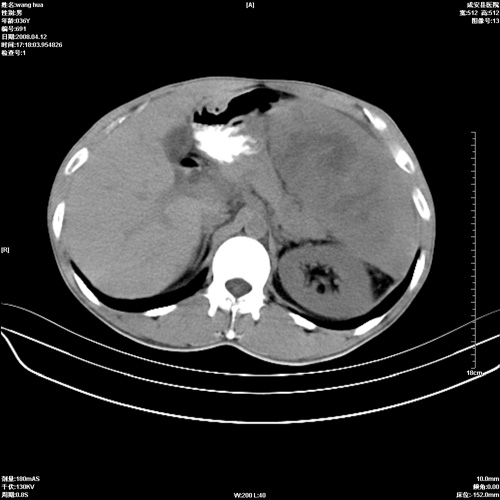

标题: CT12809:男36岁,自感上腹胀5天,B超诊断为脾肾之间占位,血 [打印本页]

标题: CT12809:男36岁,自感上腹胀5天,B超诊断为脾肾之间占位,血

确实需要强化!先大胆预测一下,来源于脾脏的占位,血管瘤或淋巴瘤可能性大。

脾脏肿瘤,有钙化,增强再说

脾脏病变,密度不均,可见钙化,考虑脾血管瘤,建议增强

脾脏明显增大,其内见巨大低密度灶,境界不清,病史较短,考虑恶性病变脾血管内皮细胞肉瘤可能。建议增强扫描与脾脏淋巴瘤及血管瘤鉴别。